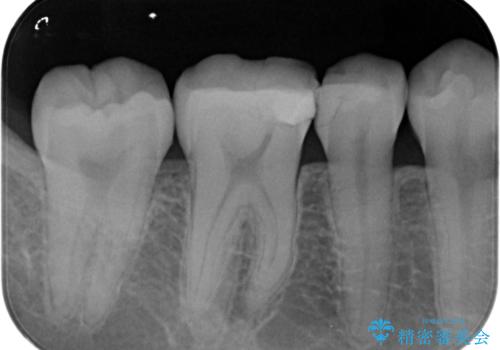

- 過去の樹脂の治療の劣化を治したいとの事で来院。大臼歯の歯は樹脂の範囲が大きくセラミックインレーで処置しても割れてしまう可能性があるため被せ物のご案内をしたところ、なるべく歯を削りたくないとのことでPGAアンレー(ゴールドアンレー)での治療となりました。手前の歯はセラミックの詰め物で治療する事ができました。

歯質の削除量をなるべく最小限にして治療が終わりました。

セラミック、ゴールド共に適合が良く虫歯の再発のリスクが低くなります。